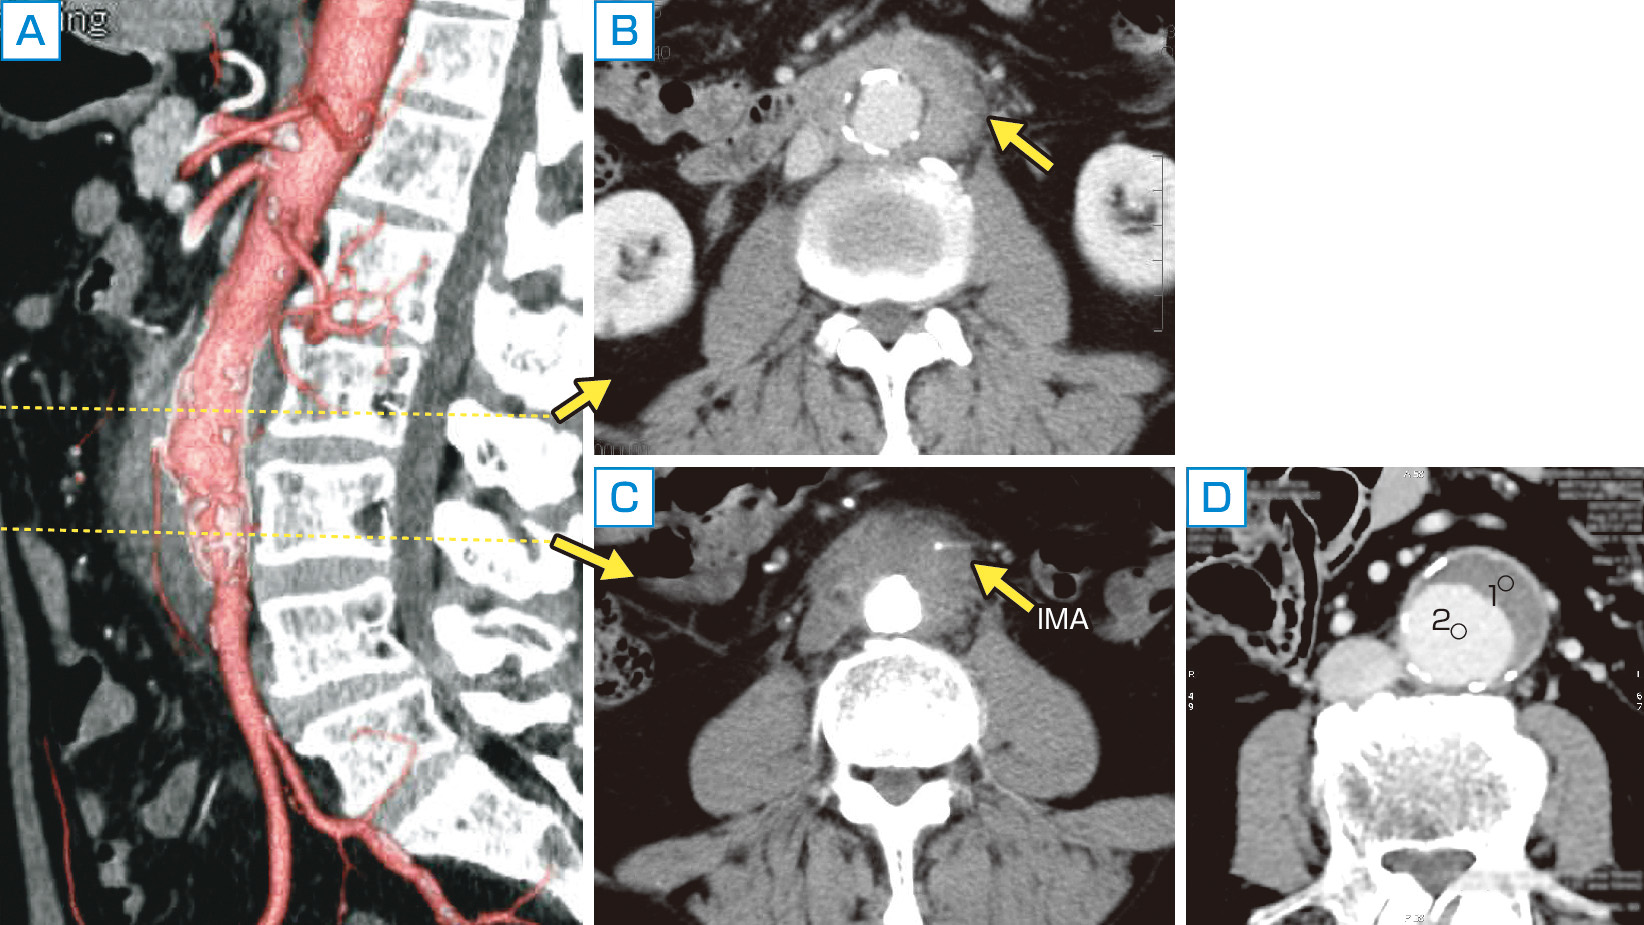

医師は、動脈の状態、閉塞の程度、動脈瘤の有無を評価するために、次の画像検査を 1 つ以上指示する場合があります。

- CTスキャン